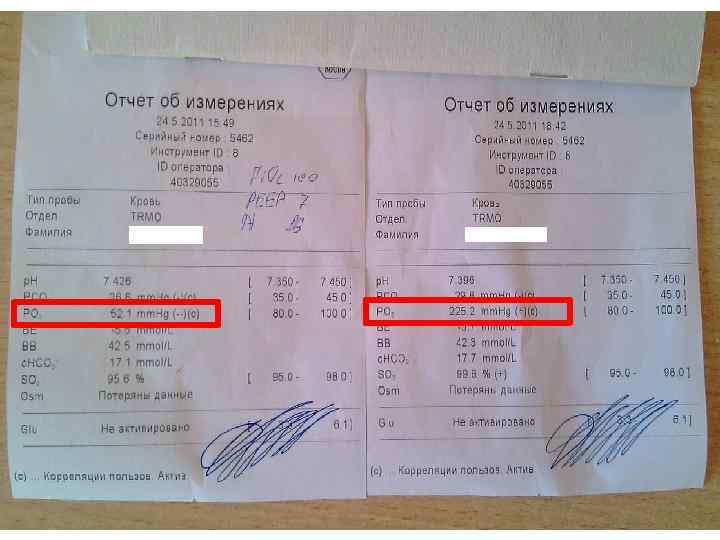

V/Q: норма и патология

V/Q: норма и патология

А можно ли «развязать» перфузию с вентиляцией? . . .

А можно ли «развязать» перфузию с вентиляцией? . . .